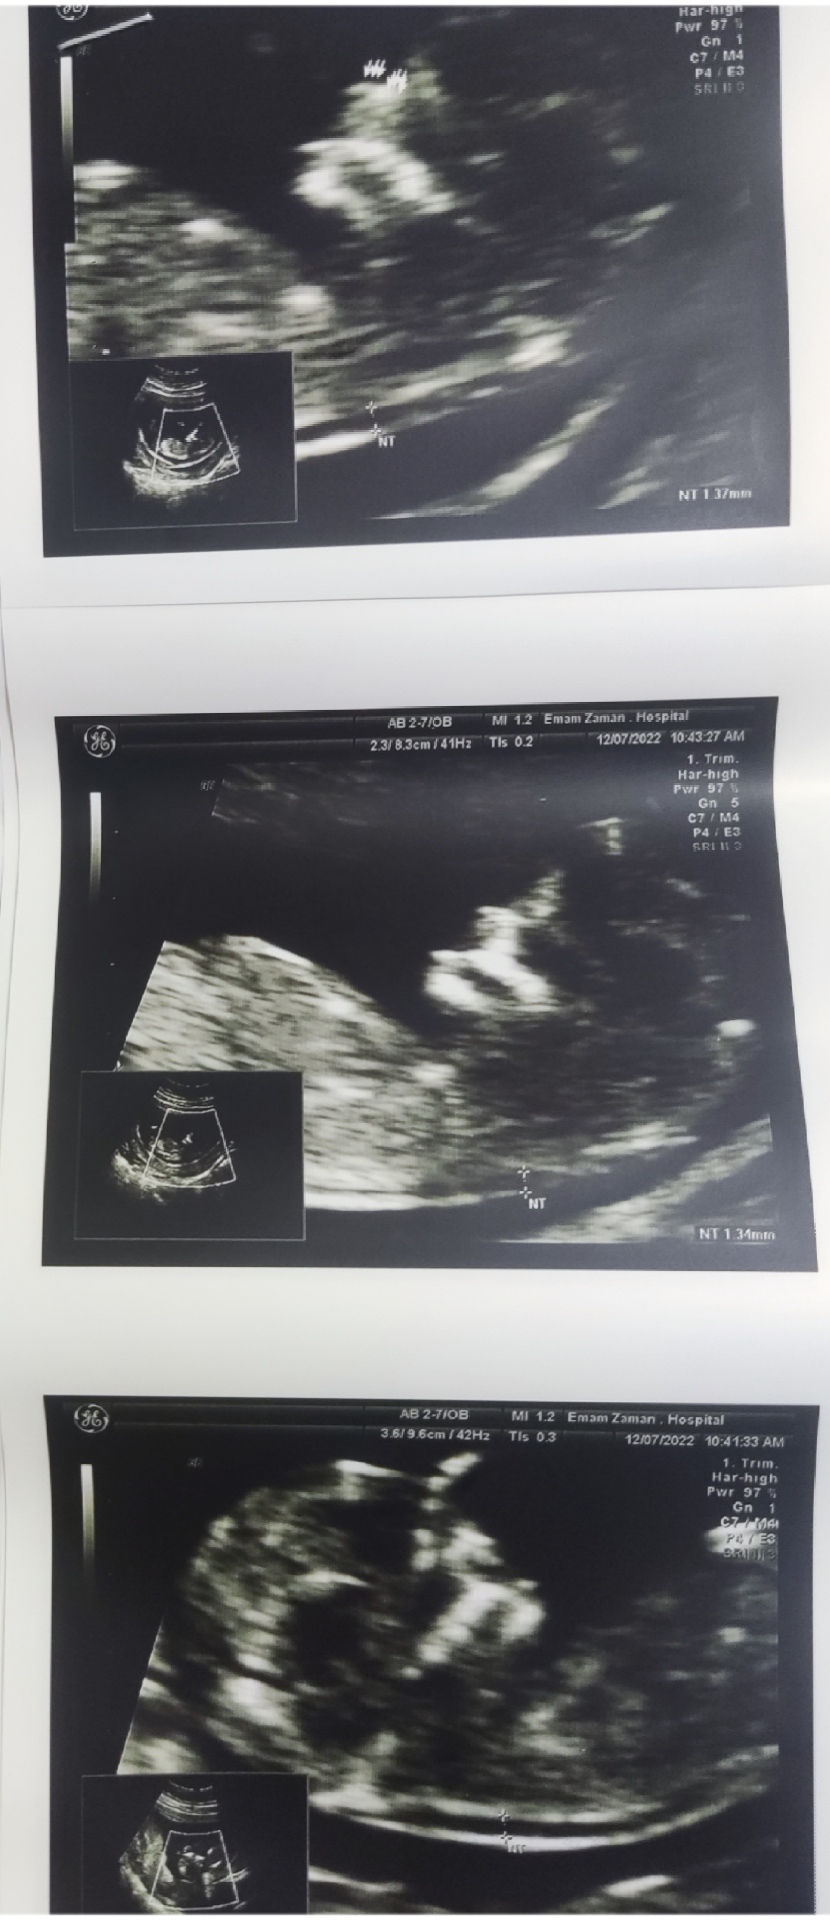

استرس براچی خب.برامن عددای ریسکم متوسط بود مجدد آزمایش دادم تا بیاد جوابش جون به لب شدم ولی هیچی نبود